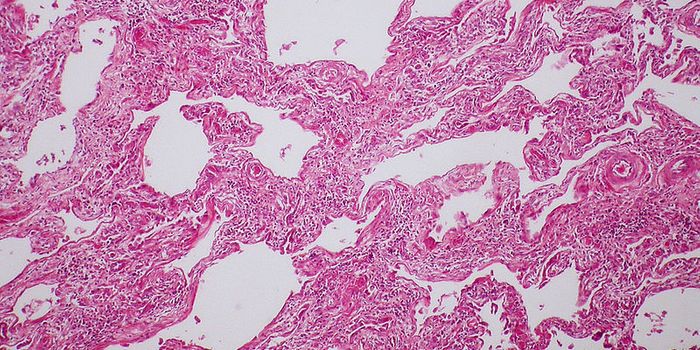

OCT 21, 2024CancerLung cancer remains a severe malignancy, expected to account for over 125,000 deaths in 2024. With high rates of m ...